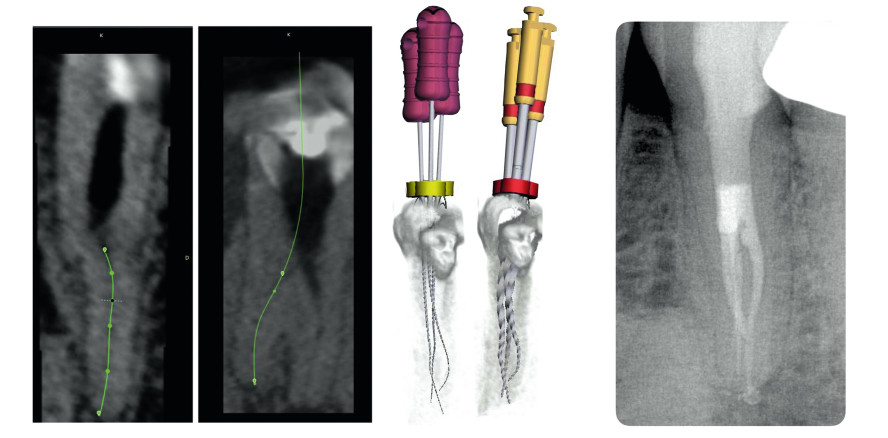

Dazu wurde eine exzentrische intraorale Aufnahme angefertigt, bei der sich zwei vestibuläre Wurzelkanäle darstellen ließen. Das Bild führte zu dem Verdacht, dass lingual noch ein dritter Wurzelkanal vorhanden sein müsste. Zur Verifizierung wurde ein kleinvolumiges DVT (Orthophos SL, Dentsply Sirona) angefertigt. Zur Darstellung ohne Kiefer- und Nachbarzähnen wird der zu behandelnde Zahn in der Software zunächst manuell separiert. Die Wurzelkanaleingänge und röntgenologischen apikalen Foramina werden in der axialen Ebene markiert (Abb. 2), bevor die Software automatisch den Verlauf des Wurzelkanals anzeigt. Dieser kann manuell angepasst werden.

Abb. 2: Orthophos SL DVT-Aufnahme in der 3-D-Endo-Software und Intraoralaufnahme nach der Wurzelkanalfüllung: Die exakte dreidimensionale Fallplanung hilft dabei, in den einzelnen Schritten die Behandlung virtuell zu simulieren und klinisch umzusetzen. © Dr. Tomas Lang

Durch das Platzieren von Feilen in den Kanälen kann vorab geprüft werden, ob die Wurzel durch die axiale Ausdehnung der Feile im Rahmen der Aufbereitung perforiert werden würde. Die Auswahl der Feile aus der integrierten Feilendatenbank und die transparente Darstellung der Zahnsubstanz lassen den räumlichen Verlauf der Instrumente sichtbar werden (Abb. 3).

Abb. 3: Die Intraoralaufnahme nach der Wurzelkanalfüllung entspricht in allen Details der Vorplanung. © Dr. Tomas Lang